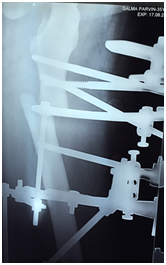

The total surgical time was about 50 minutes. There was negligible blood loss as only stab incisions were made for the schanz pins entry. Post- operative pain was well managed with just opioids for a fixed duration of three days, and on a ‘prn’ basis subsequently. She was advised partial-weight bearing mobilization the day after surgery, and over the course of the translation period. The translation process was ceased after five days when radiographs showed good bony contact and alignment in both coronal and sagittal planes. Thereafter she was encouraged for full-weight bearing with a use of aid when required (Figure 3).

Figure 3 Radiograph in the sagittal view at day 5 of translation showing a well approximated fragment.